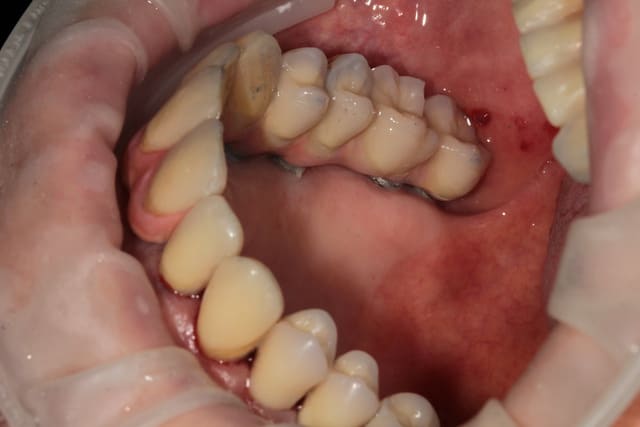

barre transvissée, chapes télescope, fausse gencive céramique au contact gingival et fausse gencive résine au collet des dents.

est-on sensés voir la liaison céram/résine sur la première photo ? si oui re-respect ....

sur les photos il s'agit bien de la liaison céram/résine c'est simple, pour le moment la limite ne se voit pas.